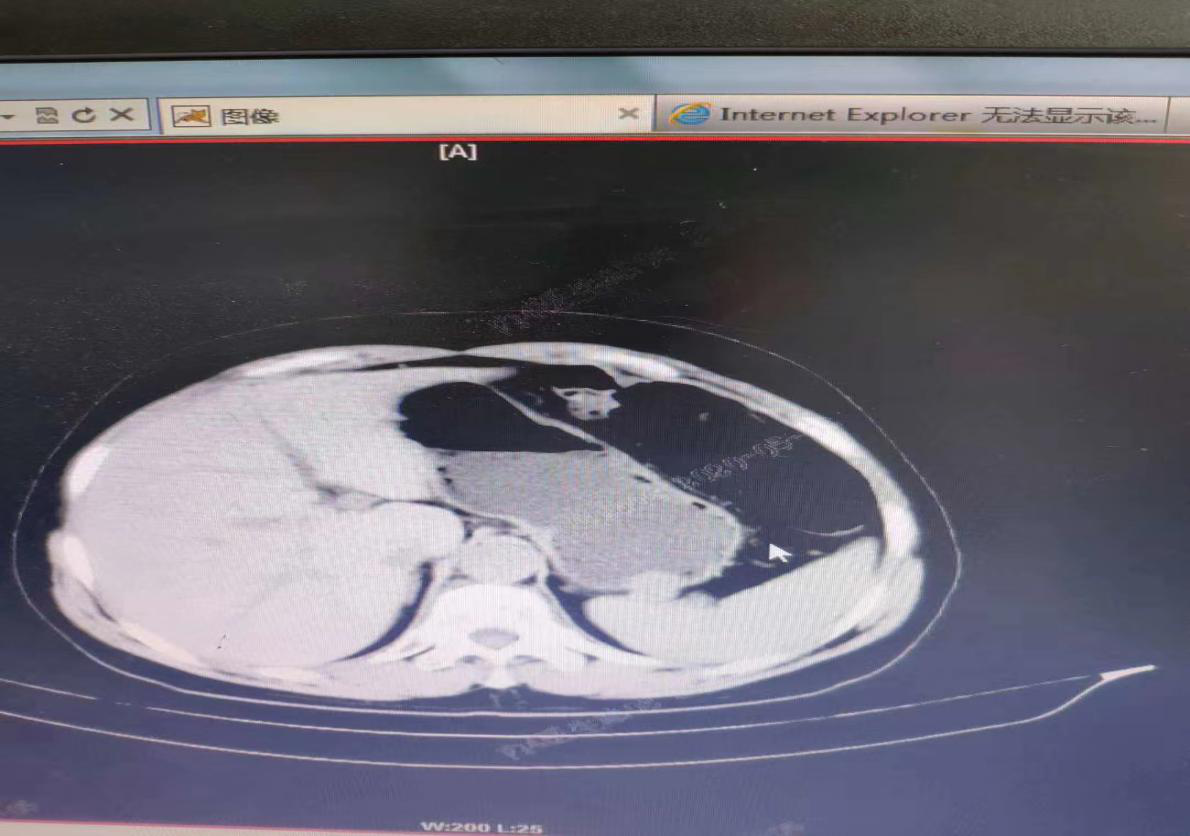

此患者于2020年5月6日在我院常规胃镜检查发现胃底1枚直径约2cm粘膜下隆起样病变,经完善上腹部CT发现此肿瘤向胃壁内外生长,考虑间质瘤可能性大,经科室反复讨论,患者有肿瘤切除指征,考虑外科手术创伤大,患者及家属要求微创手术治疗,经消化内科团队反复讨论后决定,实施经胃镜下肿瘤切除,因肿瘤向胃壁外生长,故要完整切除肿瘤,需将胃壁全层切除后再缝合,2020年5月9日下午在麻醉科的协助下,消化内科团队成功完整剥离肿瘤,手术顺利完成。术后患者生命体征平稳,未诉特殊不适。此手术的成功标志着我院消化内科在内镜诊疗技术方面又上了一个新台阶。